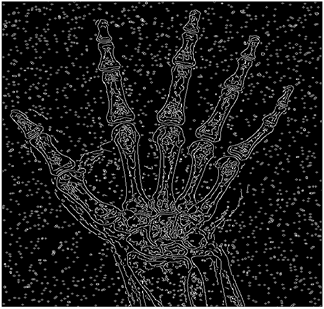

5. Results and Discussions

For the purpose of simulation, we consider two sets of images: (1) three images from MATLAB repository (Table 4) and (2) five X-ray images available online (Table 5).

As shown in Table 6, the PFOM values related to the smooth composition are higher than those of the standard composition in all cases. Table 7, Table 8, Table 9, Table 10, Table 11, Table 12, Table 13 and Table 14 also provide a visual demonstration supporting this conclusion. As is quite obvious from these tables, the density of noise in the edge-detected images of smooth composition is always less than that of the standard composition. Furthermore, the Canny edge detector is also highly prone to noises and is unable to decrease the noise density.

For Table 11, Table 12 and Table 13, the same points of Table 10 can be made. Therefore, for the sake of brevity, the points are not mentioned.

Table 13. Edge-detected image of “X-ray 4” after binarization for different noises.

NoiseCannyStandardSmooth

No noise Mathematics 10 02421 i135 Mathematics 10 02421 i136 Mathematics 10 02421 i137

G(0.001) Mathematics 10 02421 i138 Mathematics 10 02421 i139 Mathematics 10 02421 i140

G(0.002) Mathematics 10 02421 i141 Mathematics 10 02421 i142 Mathematics 10 02421 i143

G(0.003) Mathematics 10 02421 i144 Mathematics 10 02421 i145 Mathematics 10 02421 i146

I(0.25%) Mathematics 10 02421 i147 Mathematics 10 02421 i148 Mathematics 10 02421 i149

I(0.5%) Mathematics 10 02421 i150 Mathematics 10 02421 i151 Mathematics 10 02421 i152

I(1%) Mathematics 10 02421 i153 Mathematics 10 02421 i154 Mathematics 10 02421 i155